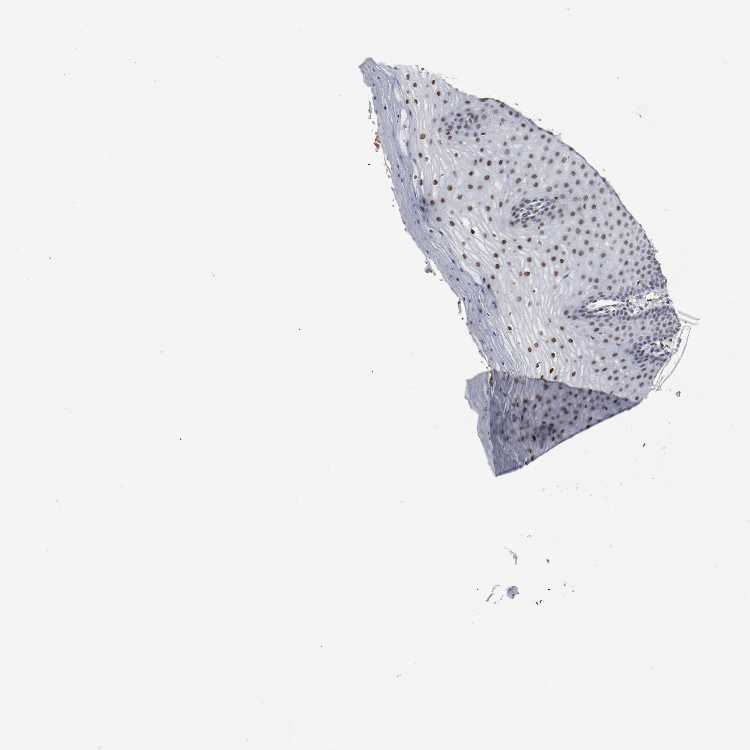

CERVIX - Antibody stainingi

Antibody staining in the annotated cell types in the current human tissue is reported as not detected, low, medium, or high, based on conventional immunohistochemistry profiling in selected tissues. This score is based on the combination of the staining intensity and fraction of stained cells.

Each image is clickable and will lead to virtual microscopy that enables deeper exploration of all samples and also displays staining intensity scores, fraction scores and subcellular localization as well as patient and tissue information for each sample.

Antibody HPA063029Antibody CAB005268

Glandular cells HighMedium

Squamous epithelial cells -High